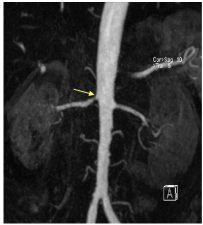

Les lésions athéromateuses (figure 37.1) se caractérisent par des sténoses :

- ostiales ou para-ostiales ;

- courtes ;

- volontiers asymétriques ;

- volontiers associées à des lésions athéromateuses de l’aorte.

Fig. 37.1 Exemple d’angio-IRM montrant une sténose ostiale à l’origine de l’artère rénale droite associée à des irrégularités de calibre de l’aorte dans ce cas de sténose athéromateuse.

Source : CERF, CNEBMN, 2022.